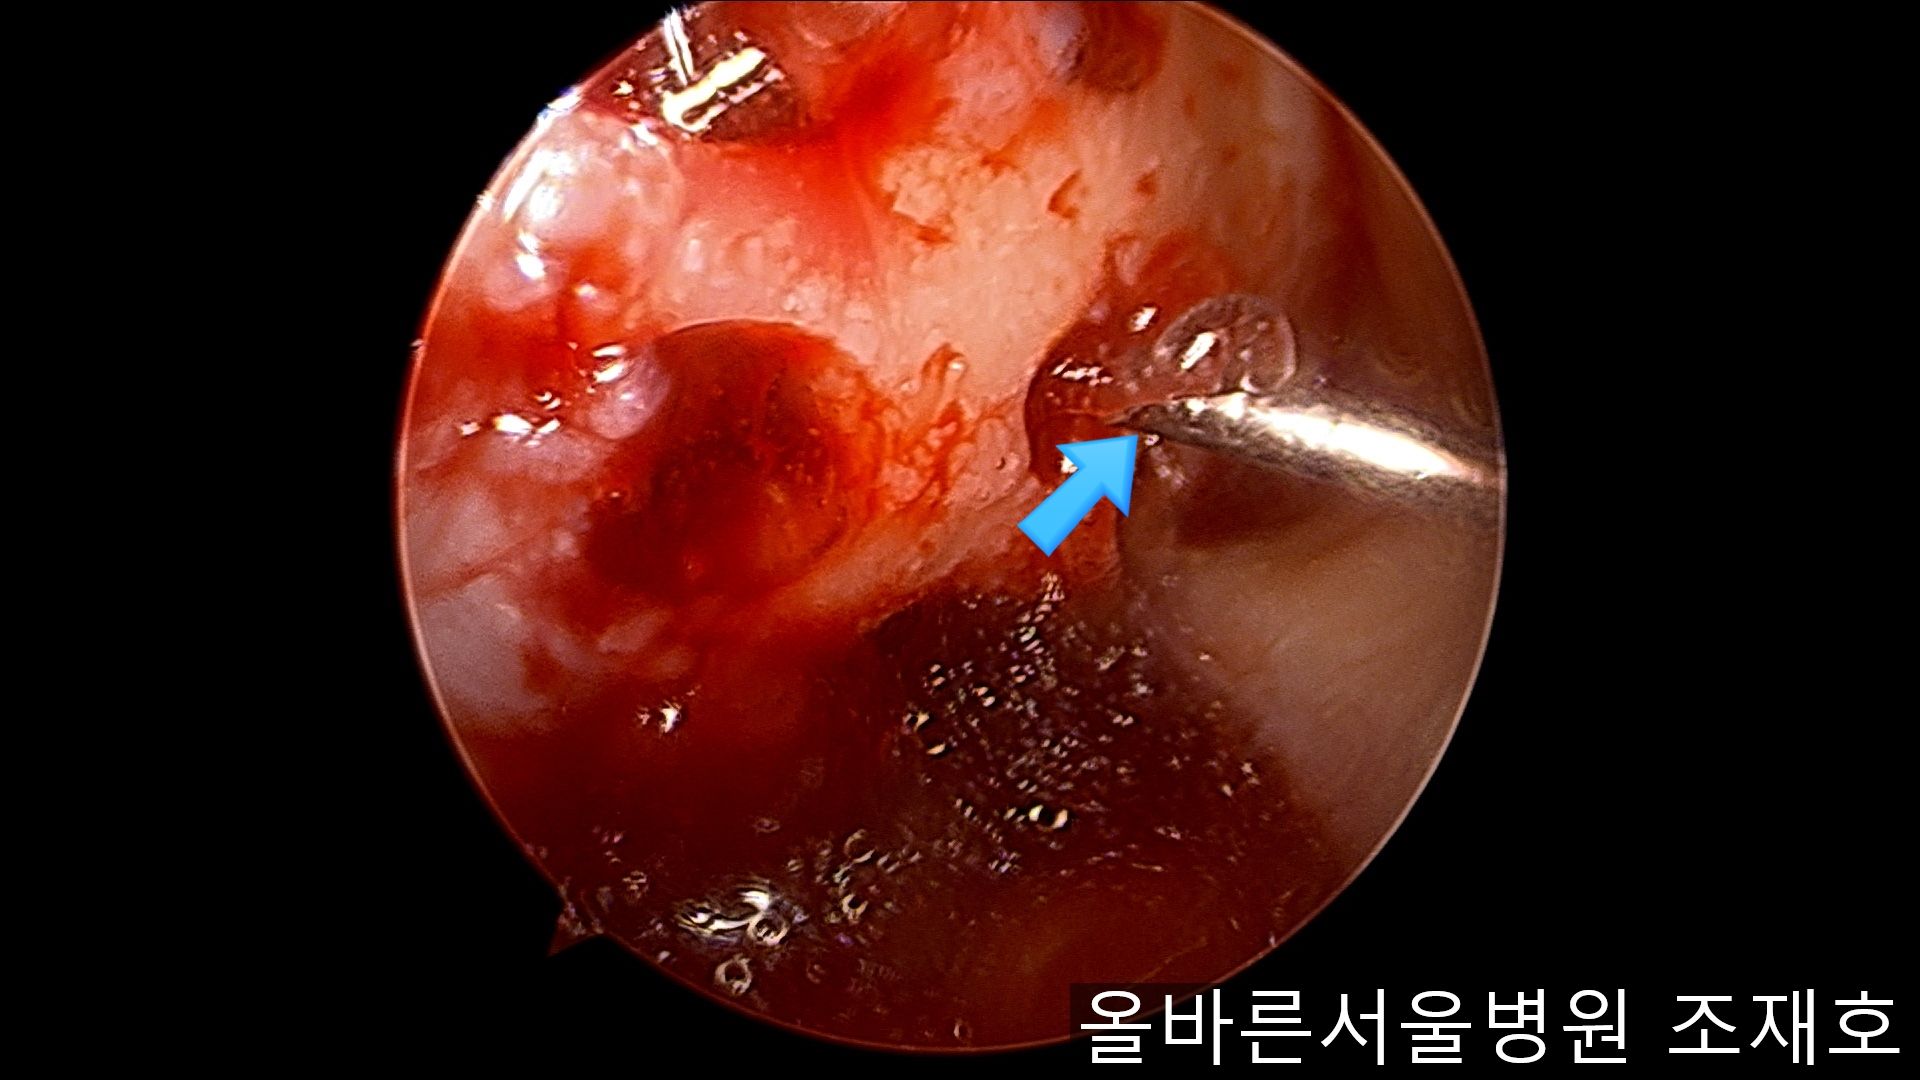

通过关节镜图像可看到:由于内侧股骨髁软骨损伤骨头已经显露出来。

胫骨上端的软骨损伤严重,也露出了骨头。

正是缺失软骨的部位碰到一起,引发剧烈疼痛,腿部逐渐变形。

为了软骨再生,在胫骨上端进行微骨折术。

胫骨上端是通过微骨折术,可再生软骨的地方。

尽量将孔打地细密,确认此处骨髓腔内的血流出。

在股骨部位用CARTISTEM注射用4mm激光钻细密打孔,并确保软骨板不倒塌。不用切开通过关节镜即可完成手术。

如图,尽量细密打孔。